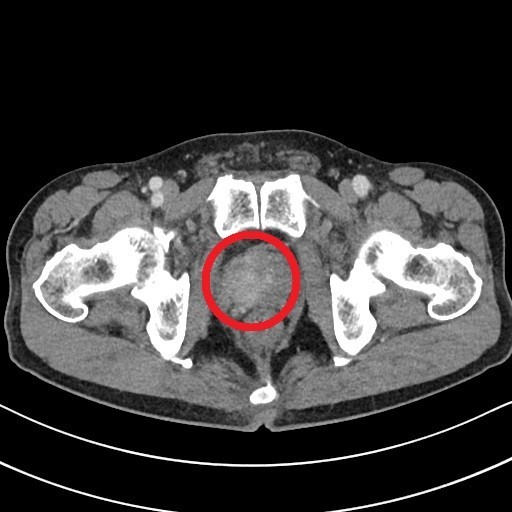

남자의 건강을 위협하는 대표 질병 중 한 가지는 전립선 질병이다. 전립선염은 남자의 50%가 일생에 한 번은 겪어볼 정도로 흔한 질병이 됐으며, 전립선암은 최근 20년간 20배 넘게 증가할 정도로 대중적인 질환이 되었는데요.